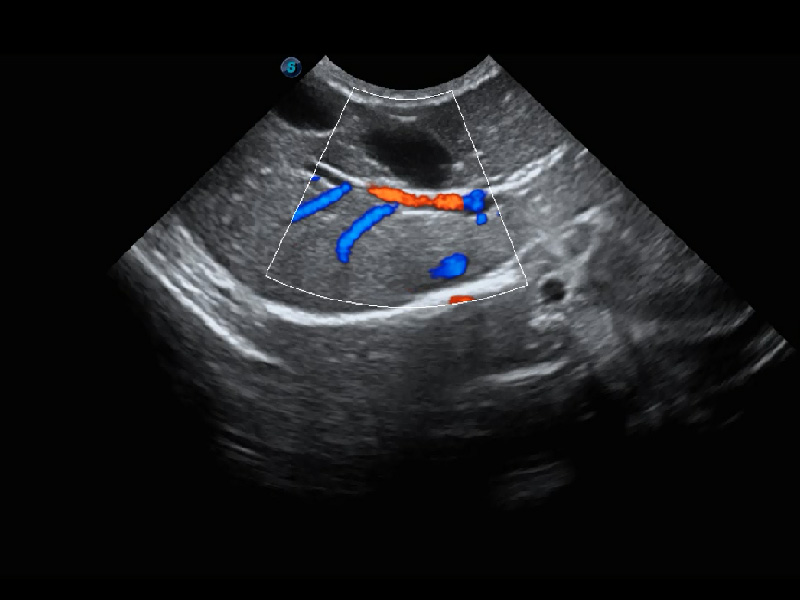

(猫)髂动脉血流频谱

(犬)肾脏血流